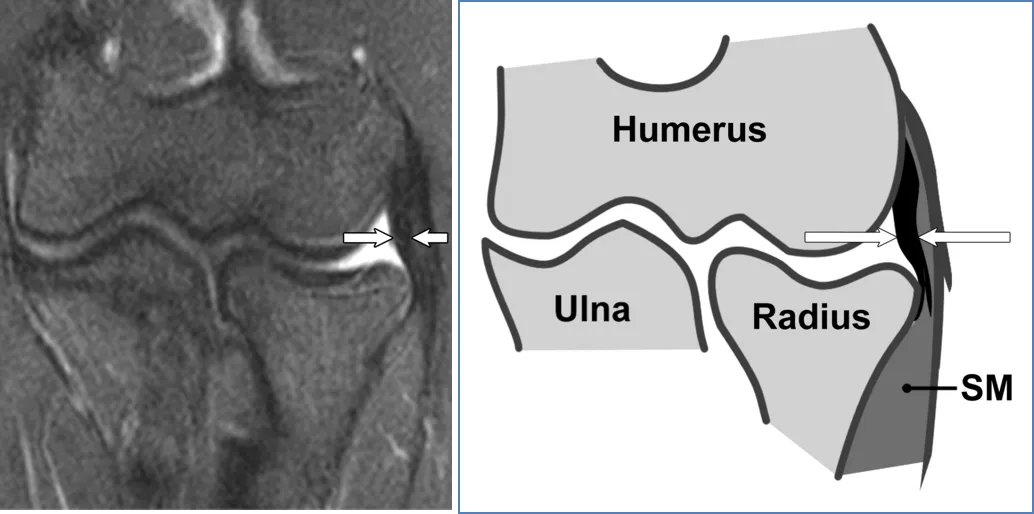

桡侧副韧带(RCL):

RCL。(a)28岁男性的冠状STIR磁共振成像。RCL外观均匀(箭头)。(b) RCL对应示意图(箭头)。SM = 旋后肌。